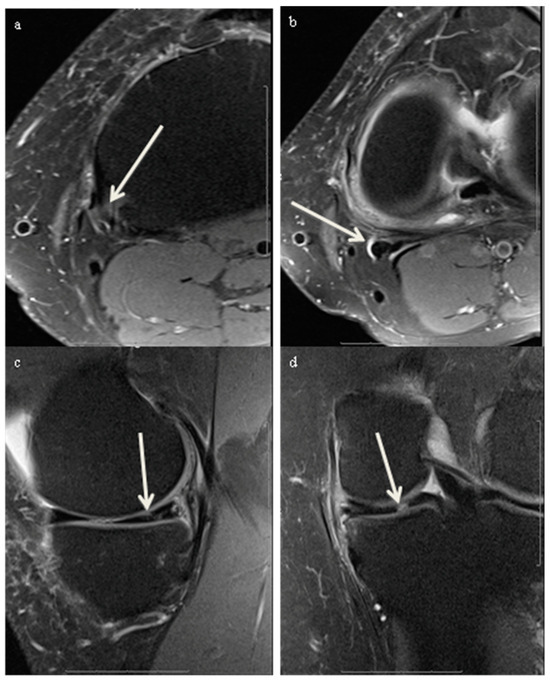

2.4. Qualitative Image Analysis